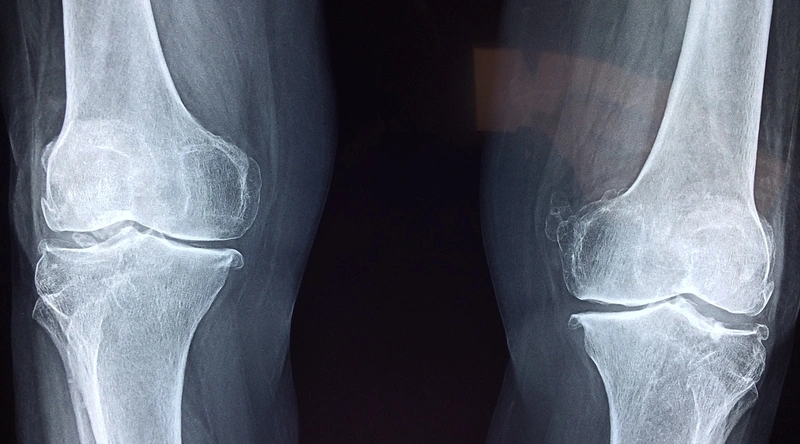

고관절 통증의 가장 일반적인 원인 중 하나는 바로 노화로 인한 퇴행성 변화입니다. 나이가 들면서 관절의 연골은 자연스럽게 닳게 되고, 이로 인해 관절 간의 마찰이 증가합니다. 이러한 마찰은 통증을 유발하고, 고관절의 가동 범위를 제한할 수 있습니다. 특히 50세 이상의 연령대에서 이러한 현상이 두드러지며, 결국 퇴행성 고관절염으로 발전할 가능성이 높습니다. 따라서 정기적인 건강검진과 예방 조치가 필요합니다.

수술적 치료

보존적 치료로 호전이 없거나, 고관절의 연골이 심하게 손상된 경우에는 수술이 필요할 수 있습니다. 인공관절 치환술은 통증을 줄이고 관절 기능을 회복하는 데 효과적입니다. 수술적 치료는 환자의 상태에 따라 맞춤형으로 진행되며, 결과적으로 환자의 삶의 질을 개선하는 데 기여합니다.